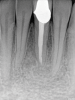

In addition to preoperative factors, treatment-related factors are tied to prognosis following SRETX. Traditional surgical techniques have a reduced prognosis compared to modern microsurgery techniques (59% vs 94%). Modern techniques allow for greater precision and include the use of a microsurgical instrument along with a surgical operating microscope for magnification and illumination.30,31 Under magnification, anatomical details of a resected apex surface can be easily visualized, including isthmuses, canal fins, microfractures, and lateral canals (Figure 9 and Figure 10).30,31 Furthermore, under microscopy, access to the apex requires less apical bone removal, facilitating the development of smaller bony crypts. Decreased crypt size is associated with faster healing.25 Ultrasonic instruments aid in the creation of parallel, deep preparations with a shallow bevel and precise apical fillings that improve the prognosis of SRETX.30,31

Fig 9 and Fig 10. Modern microsurgical techniques enhance the success rate of surgical retreatment through improved magnification, illumination, and the creation of optimal preparation and root-end filling. Fig 9: Postoperative periapical radiograph following apical surgery. Fig 10: Periapical radiograph at 18-month follow-up showing bony healing.

Figure 9

Fig 10. Modern microsurgical techniques enhance the success rate of surgical retreatment through improved magnification, illumination, and the creation of optimal preparation and root-end filling. Fig 9: Postoperative periapical radiograph following apical surgery. Fig 10: Periapical radiograph at 18-month follow-up showing bony healing.

Figure 10